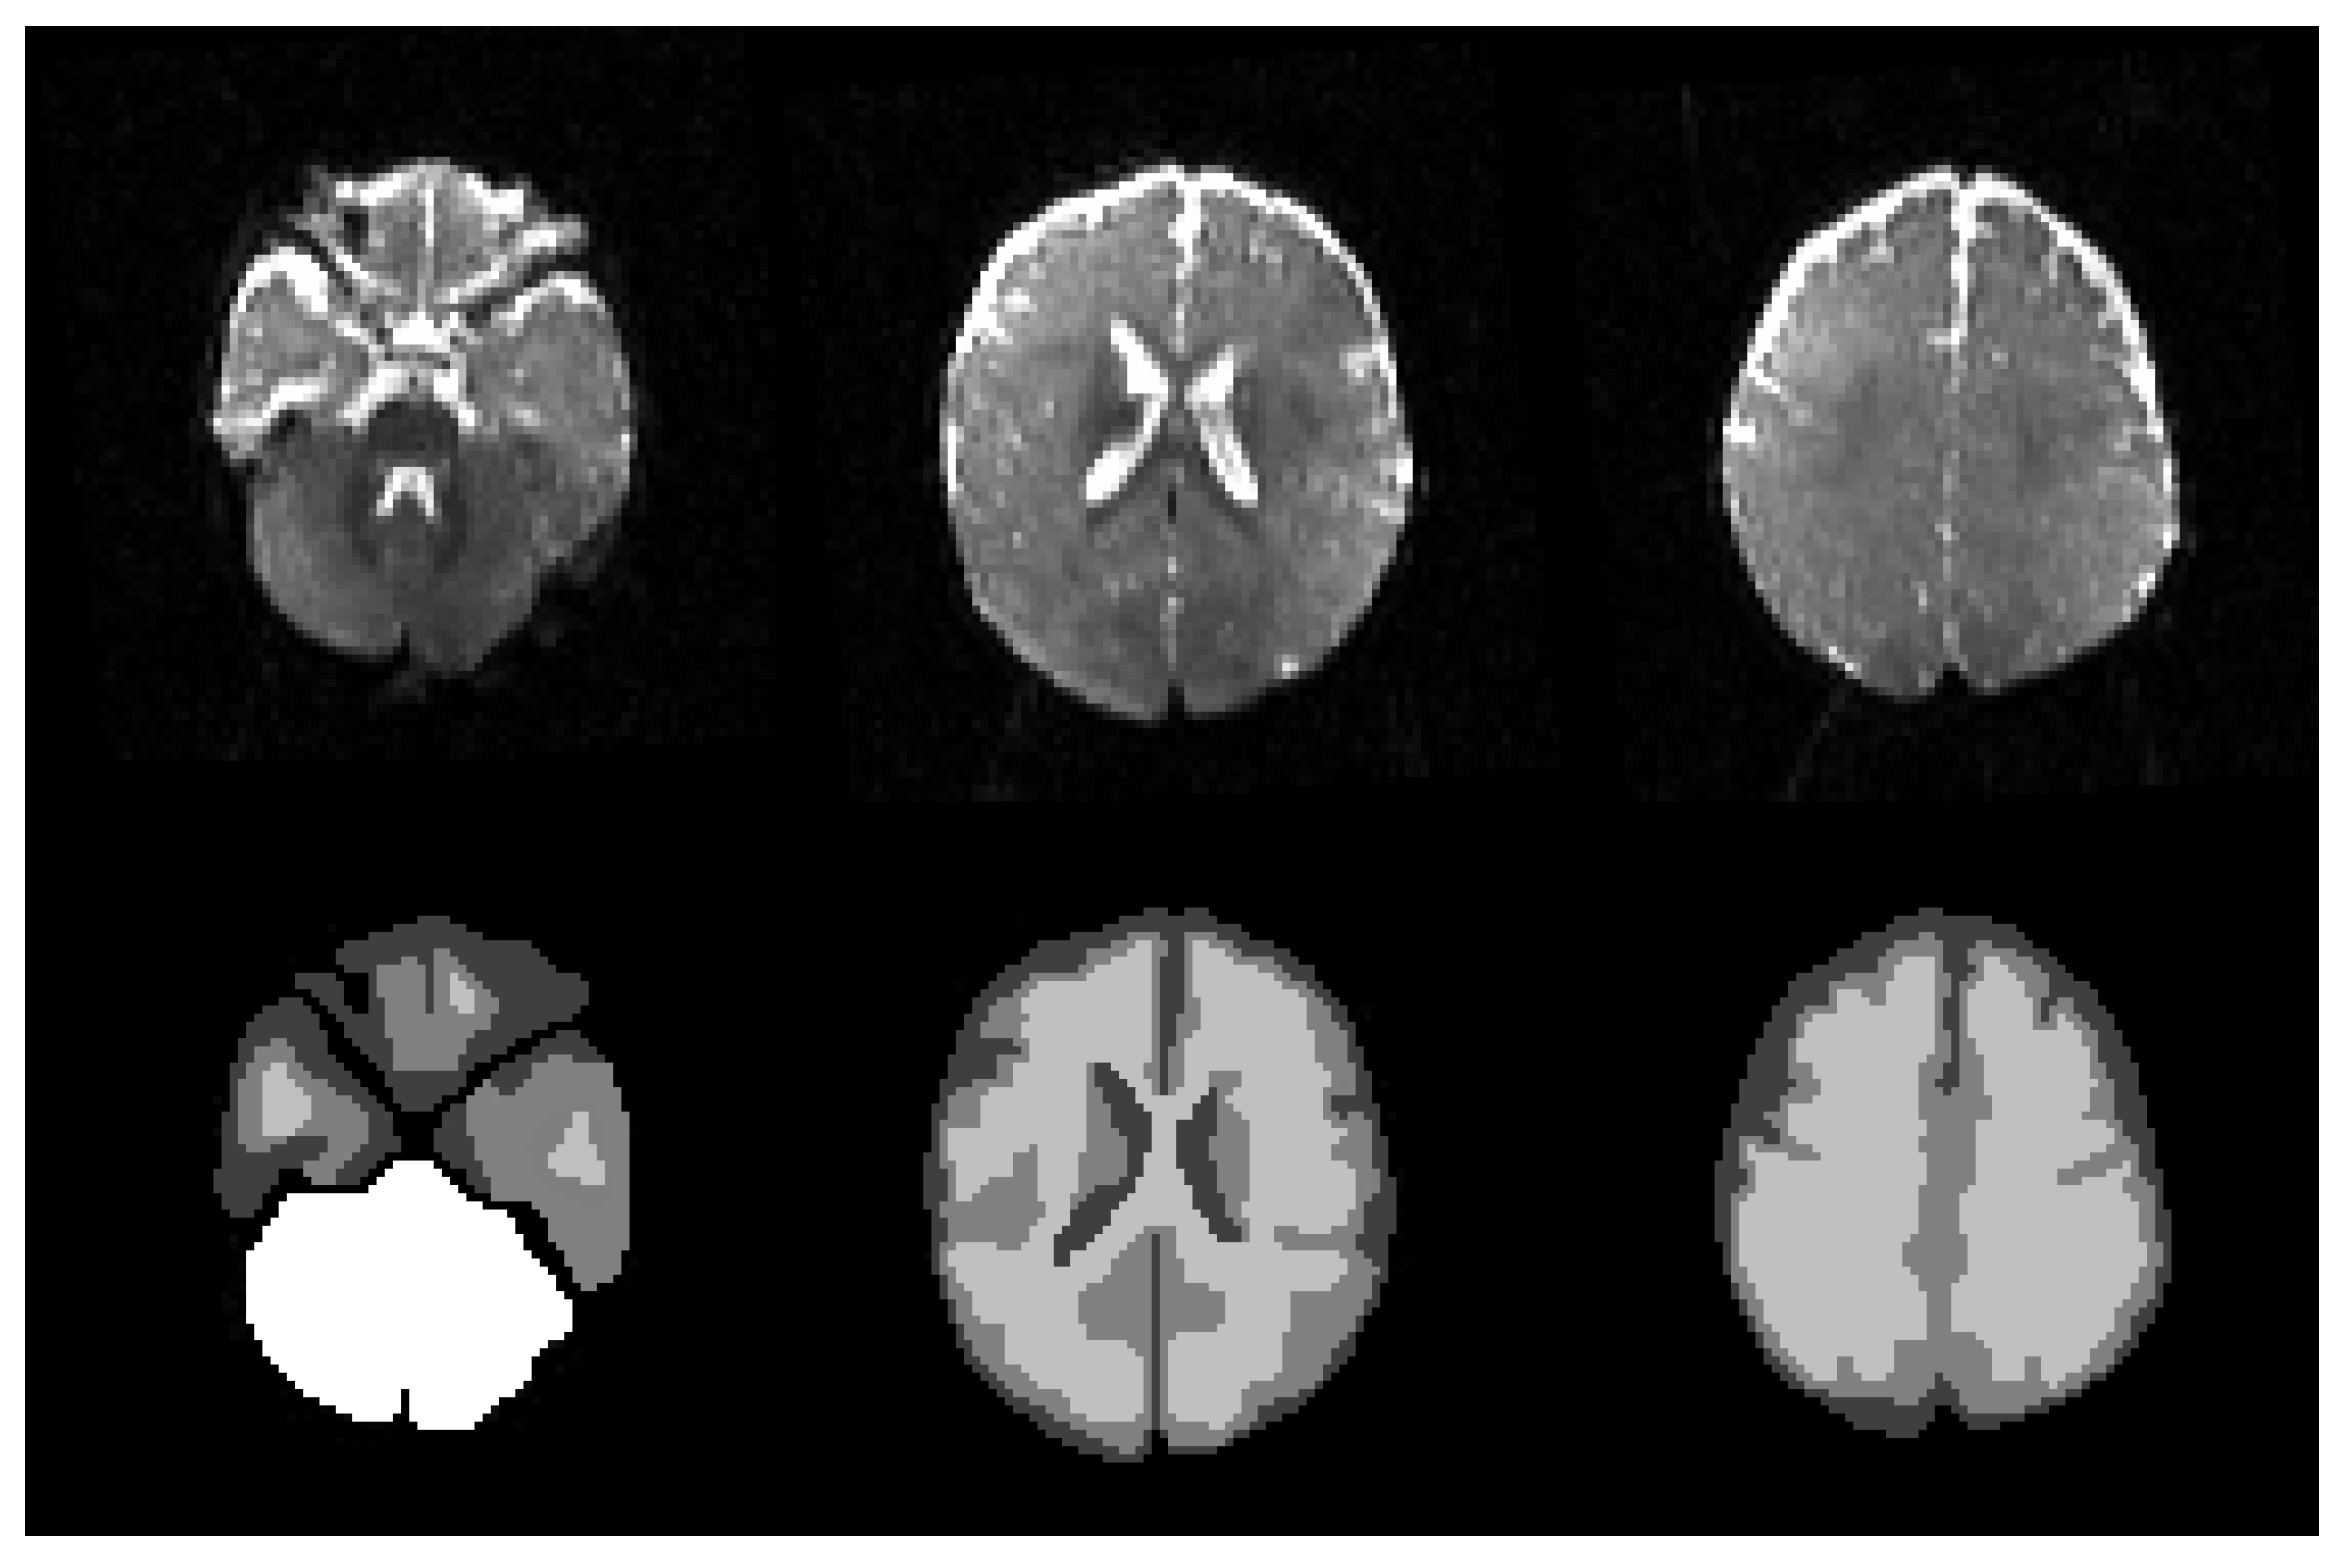

Segmentation Results